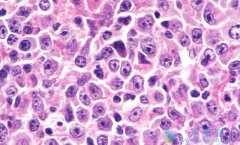

弥漫性大B细胞淋巴瘤是目前最常见的成人非霍奇金恶性淋巴瘤,占西方国家成人非霍奇金恶性淋巴瘤的30~40%,在发展中国家,所占的比例更高,达60%。在儿童淋巴瘤中,DLBCL所占的比例在10%以下。DLBCL发病年龄范围很广,平均发病年龄70岁,但亦可见于儿童; ...